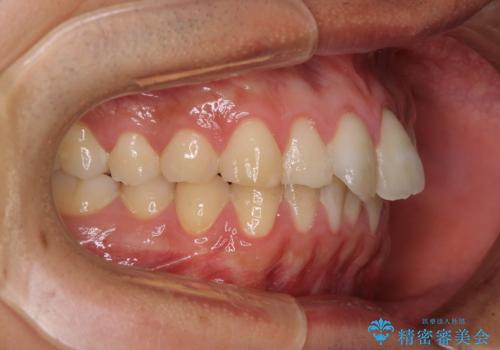

- 上下前歯のデコボコと、それに伴う出っ歯を気にして来院された患者様です。

インビザラインによる上下歯列の側方拡大と後方移動、IPR(歯と歯の間を削る)にるスペースの獲得により歯列を整えることとしました。

歯と歯の間を削ることでうまくスペースコントロールでき、また、毎日22時間以上しっかりとマウスピースを装着していただいたので、スムーズに治療が進みました。